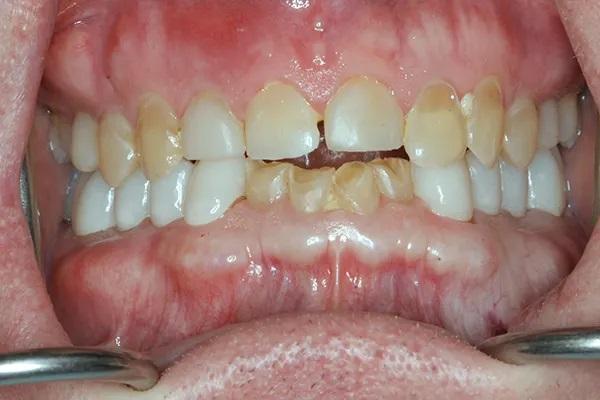

Мужчина, 54 года, был направлен к автору по поводу истирания зубных рядов и эрозии, которые, как предполагалось, были вызваны выраженным бруксизмом (Фото 1 и Фото 2). Его лечащий врач не был уверен, с чего начать планирование лечения, из-за предполагаемой сложности случая. Основной проблемой пациента был страх потерять часть или все зубы из-за обширного разрушения эмали (Фото 3). Были собраны снимки и подробные медицинские и стоматологические истории болезни, а также проведено детальное клиническое обследование. Полные снимки, фотографии и цифровые сканы были отправлены в зуботехническую лабораторию, и был разработан план лечения. У пациента было сильное желание действовать, и он принял этот план. Клинический случай был разбит на сегменты для обеспечения предсказуемой и более удобной реконструкции.

Фото 2: Максимальный бугорково-фиссурный контакт зубов-антагонистов до лечения. Обратите внимание на эрозию шейки и потерю эмали, не связанные с окклюзией.